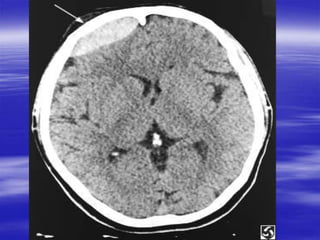

Pemeriksaan

 Pemeriksaan penunjang;

Rontgen kepala AP/Lat

Head CT Scan

 Px :Roo olos,CT Scan,EEG

 Pemeriksaan: Ro Kepala,CT scan,EEG

Pemeriksaan  Stats fungsivital :ABC  Status kesadaran  Status neurologis  Pemeriksaan penunjang; Rontgen kepala AP/Lat Head CT Scan